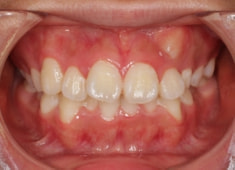

治療前